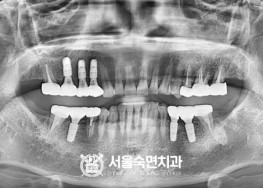

서울대학교-출신-전문의-의료진의-수많은-임플란트-수술-경험-임상으로-검증된-정품-임플란트-재료-사용

임플란트-치료-전후사진

서울대학교-출신-보건복지부-인증-통합치의학과-전문의-2인-책임관리